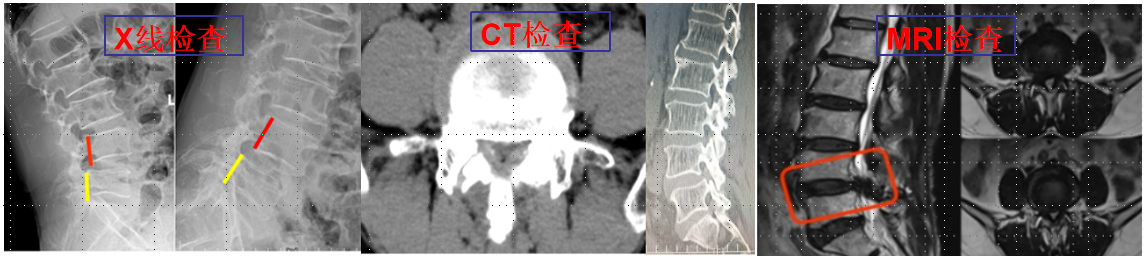

诊疗技术:

①脊柱导航技术:为脊柱微创技术更加精准高效的操作提供保障,从而减少患者创伤和痛苦。

②椎间孔镜技术:科室常规熟练开展椎间孔镜技术治疗颈、胸、腰椎椎间盘突出症、椎管狭窄症、椎管黄韧带骨化等。

③UBE技术(单侧双通道内镜技术):率先在重庆市内开展此项技术,用于治疗腰椎间盘突出症、腰椎管狭窄症、腰椎滑脱(失稳)症及颈椎病、颈椎管狭窄症等。